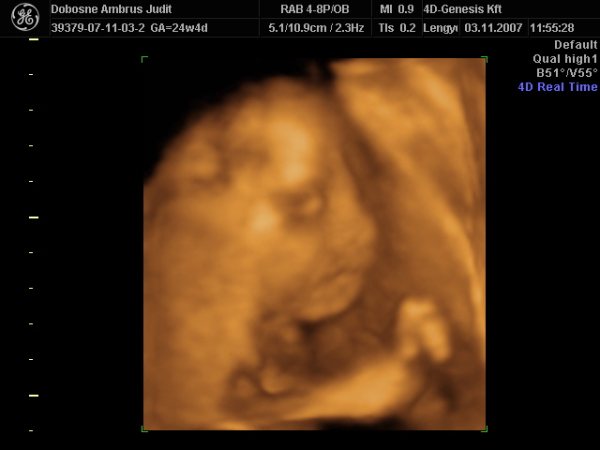

A doki szerint pufók kislány